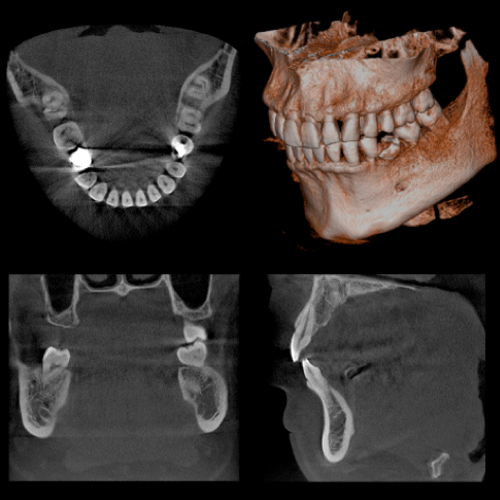

コンピュータを駆使したデータ処理と画像の再構成で、断層写真を得ることができる装置です。歯科用CTとは、近年開発された歯科に特化したCT装置で、コーンビーム方式を用いているためコーンビームCTとも言われています。従来のX線写真は二次元的な平面での診断しかできませんが、歯科用CTでは三次元の立体画像でのレベルに変わるので、より多くの情報が得られます。

一般のレントゲンで見えなかった部分が容易に確認できるようになりました。顎の内部構造などもリアルに見えます。

顎や歯だけでなく、上顎洞(鼻の奥)の形態や粘膜の状態、病巣などを立体画像で確認できます。

親知らずや、埋伏歯の診断に利用することで、立体的に歯の位置や、顎骨の状態、周囲の神経や血管の管との関係を明確に診断できます。 それにより治療の安全性が高まり、患者様にとっても有益となります。のう胞や腫瘍に関しては、その位置や大きさなどを立体的に確認でき、その後の治療計画、処置に役立ちます。顎関節症、歯性上顎洞炎などの疾患に関しても、今までのレントゲンでは得られなかった情報を得れることで診査診断、治療に多く貢献できます。